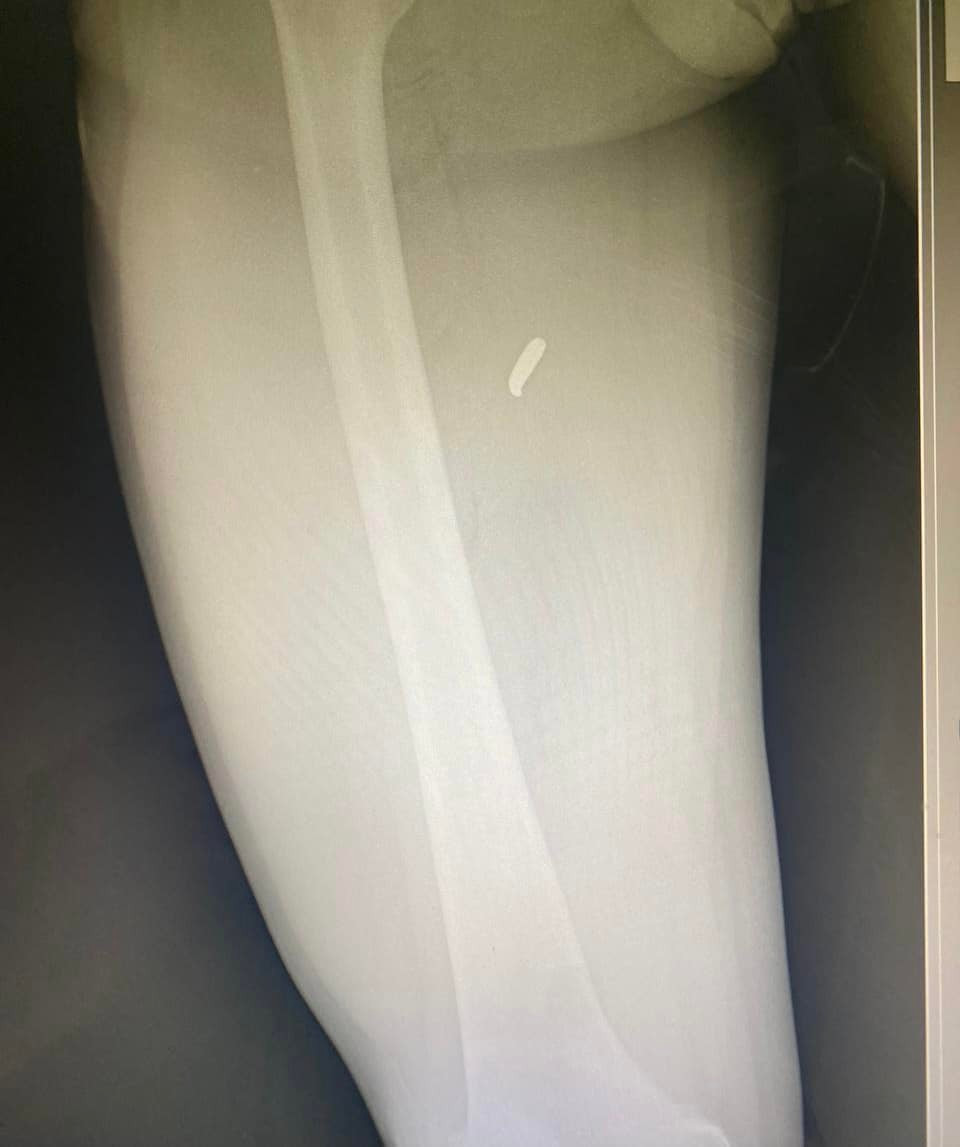

Хуан сидів на задньому сидінні і встиг пригнутися — куля поранила його в стегно.

Севгіль Мусаєва: 13 березня - День, коли час зупинився - зображення

Брент сидів попереду. Куля пройшла крізь шию. Він загинув на місці.